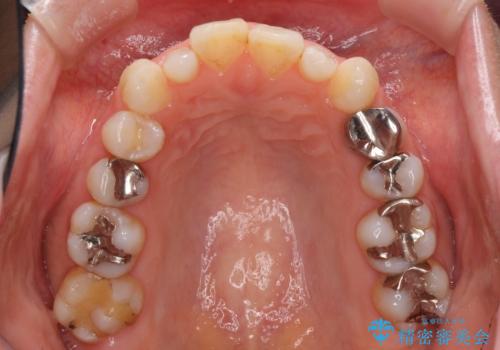

- 前歯のデコボコと矮小歯、更には痛みを感じる奥歯のむし歯を気にして来院された患者様です。

奥歯には根管治療が必要な歯があり、上顎側切歯は左右ともに矮小歯でした。

上下前歯のデコボコはワイヤーでもインビザラインでも対応可能でしたが、補綴治療が多く必要となることから、インビザラインでの矯正治療を行いながら、並行して補綴治療を行うこととしました。

まずは根管治療を行った上で矯正治療用の仮歯を装着し、矯正治療後半に補綴治療を並行して行うこととしました。